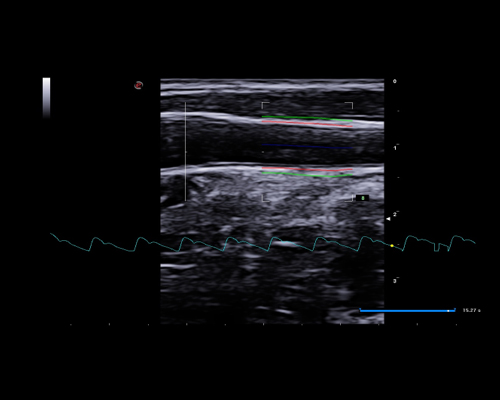

Research and successfully implement the limitless ultrasound technologies such as MicroE – Detect microcalcification; Xstrain4D – Cardiac strain 4D; XSTIC – Spatial-Temporal Image Correlation

MyLab X8 eXP integrates latest technologies, delivering high level of image quality with optimal workflow, efficiency